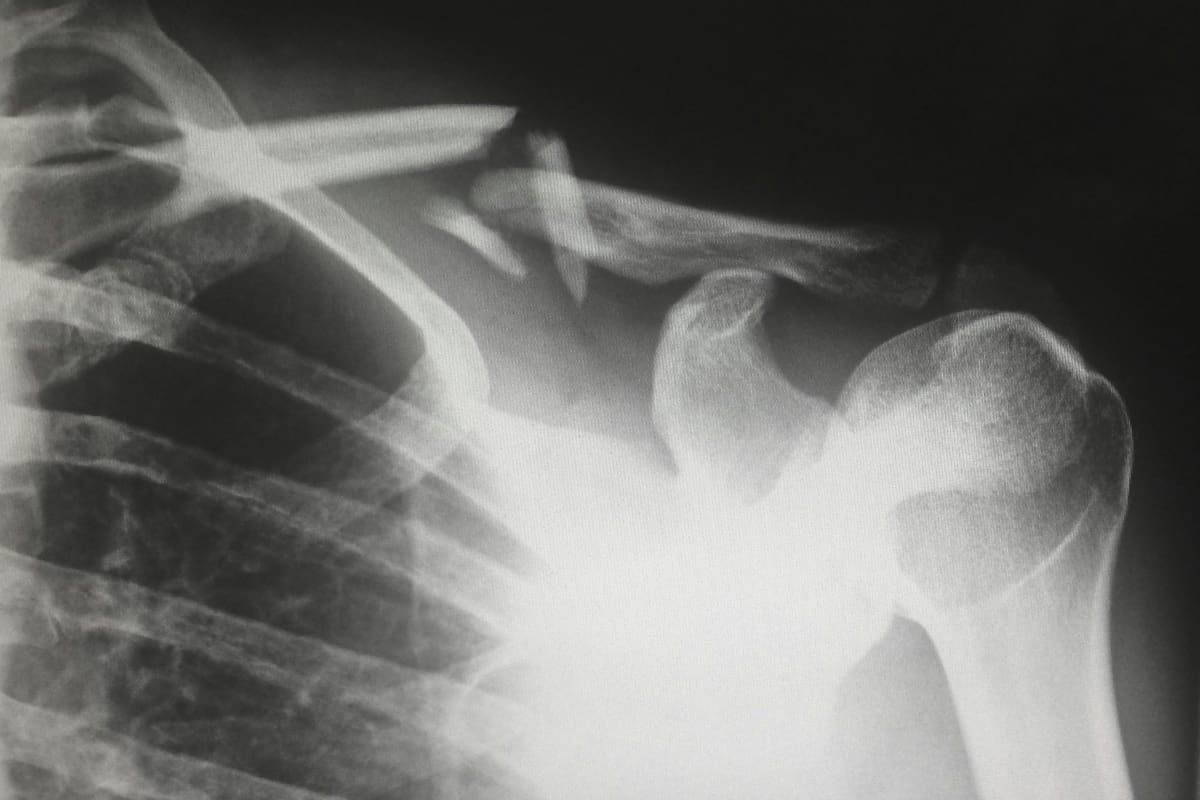

Para muchas personas, la palabra osteoporosis se asocia con adultos mayores o mujeres después de la menopausia. Sin embargo, especialistas en endocrinología alertan que la diabetes mellitus, tanto tipo 1 como tipo 2, incrementa el riesgo de fracturas de columna y cadera entre dos y cuatro veces, incluso cuando la densidad ósea parece normal en los estudios.

Este fenómeno ha sido descrito como una “osteoporosis silenciosa”, ya que no siempre se detecta con una densitometría ósea convencional y suele manifestarse solo cuando ocurre una fractura.